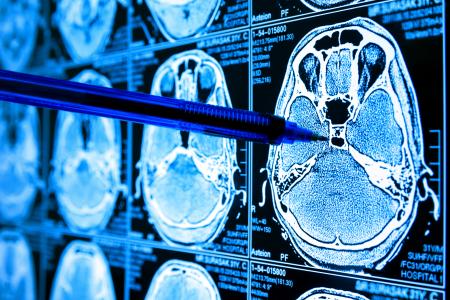

La barrière hémato-encéphalique est un réseau spécialisé de vaisseaux sanguins et de cellules cérébrales qui constitue le système de protection du cerveau contre l'invasion de toxines et de microbes dangereux. Elle peut être ouverte temporairement grâce à un appareil d’échographie focalisée spécialisé. Ce procédé consiste à injecter des microbulles remplies de gaz inerte dans le flux sanguin du patient. Guidées par IRM, des régions cérébrales précises sont ciblées pendant la circulation des microbulles injectées. Sous l'effet d'ondes ultrasonores de faible intensité, les microbulles oscillent au sein du champ énergétique, provoquant des perturbations mécaniques temporaires dans les parois des vaisseaux sanguins cérébraux.

L’étude est menée auprès de 34 patients atteints de glioblastome ayant reçu des ultrasons focalisés guidés par IRM en association avec une chimiothérapie standard. Les patients inclus dans l'étude ont été appariés à un groupe témoin de 185 patients atteints de glioblastome, rigoureusement sélectionnés et présentant des caractéristiques similaires. Ces patients ont reçu la dose standard de témozolomide (un médicament de chimiothérapie), sans ultrasons focalisés. Tous les participants à l'essai ont d'abord subi une intervention chirurgicale pour retirer leur tumeur cérébrale, suivie de 6 semaines de chimiothérapie et de radiothérapie, puis jusqu'à 6 séances mensuelles d'ultrasons focalisés associées au témozolomide. L’analyse révèle que :